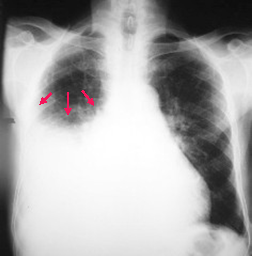

Fluid rises higher

along the edge of

a pleural effusion

producing an

upside down “U”

or meniscus

shape

Meniscus Sign